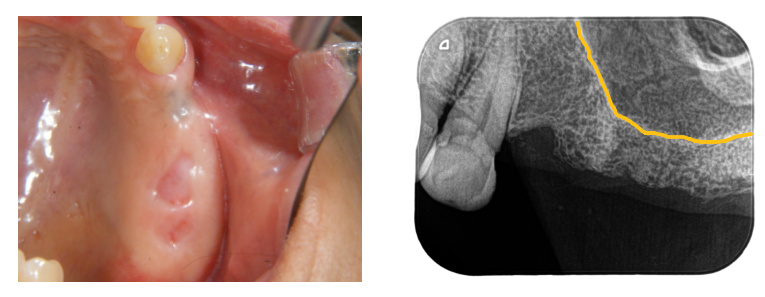

レントゲンとCTで、上顎洞という鼻とつながっている空洞の形を診査し

骨の厚さが少し足りないことが分かったため、上顎洞粘膜を挙上して

骨造成することにしました。

3本埋入しています。1本はGBRも併用しています。

3本とも上顎洞粘膜を挙上しています。

挙上は水圧で行い、挙上した部分は生理食塩水と血液で満たされています。

その血液が骨に変わります。

異物を入れないため、アレルギー反応も無く、非常に安全性の高い方法です。